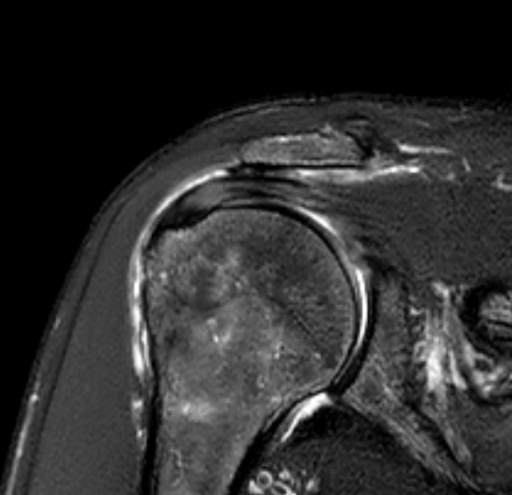

Tear of SSP and ISP?

Female 50 y.o. There is known tear of supraspinatus and infraspinatus tendon. Patient has frozen shoulder. Q1: It looks like incomplete full thickness tear of SSP, with rupture of the posterior aspect of tendon and extending to the infraspinatus? I am guessing there is tendinosis of the anterior aspect of SSP tendon but without rupture? Q2: Why the bone marrow of humerus is so bright on T2 SPAIR with prominent vessels? https://www.cmrad.com/cases/1786240110

1 like • Jul 29

I think this is a full-thickness tear mainly involving the anterior infraspinatus tendon but also some of the posterior suprapsinatus junctional fibers. I don't see how you could find any intact bursal or articular surface fibers. Definitely some underlying tendinosis. What further suggests this is more so infraspinatus is that there is already some degree of muscle bulk loss and infiltration into the infraspinatus, not much elsewhere. I agree the humeral head cysts are related to traction enthesopathy, particularly related to the infraspinatus, also noting there is some intrasubstance fluid/cyst formation dissecting into the infraspinatus muscle.